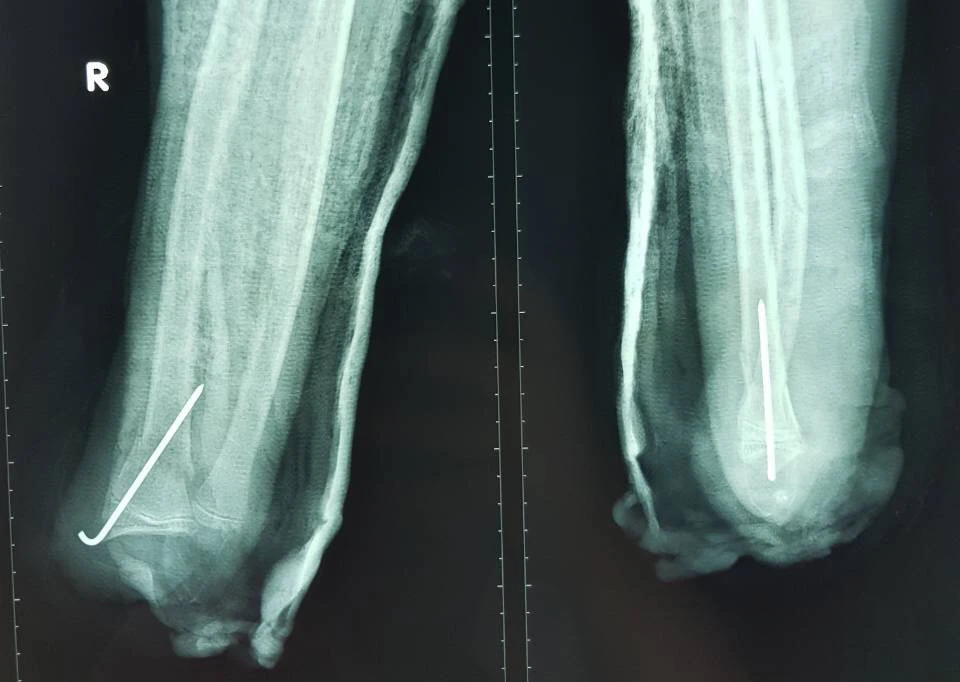

Hình chụp X-quang cho thấy xương các ngón bàn tay phải của em Đ. bị gãy nhiều đoạn nhỏ. Ảnh: HÒA KHÁNH

Trước đó, em Đ. được đưa vào BV nói trên trong tình trạng bàn tay phải dập nát. Chưa hết, các xương ngón tay gãy nhiều đoạn nhỏ. Người nhà cho biết nguyên nhân khiến bàn tay em Đ. dập nát là do pháo nổ.

Các bác sĩ buộc phải tháo khớp bàn tay phải của em Đ. Ảnh: HÒA KHÁNH